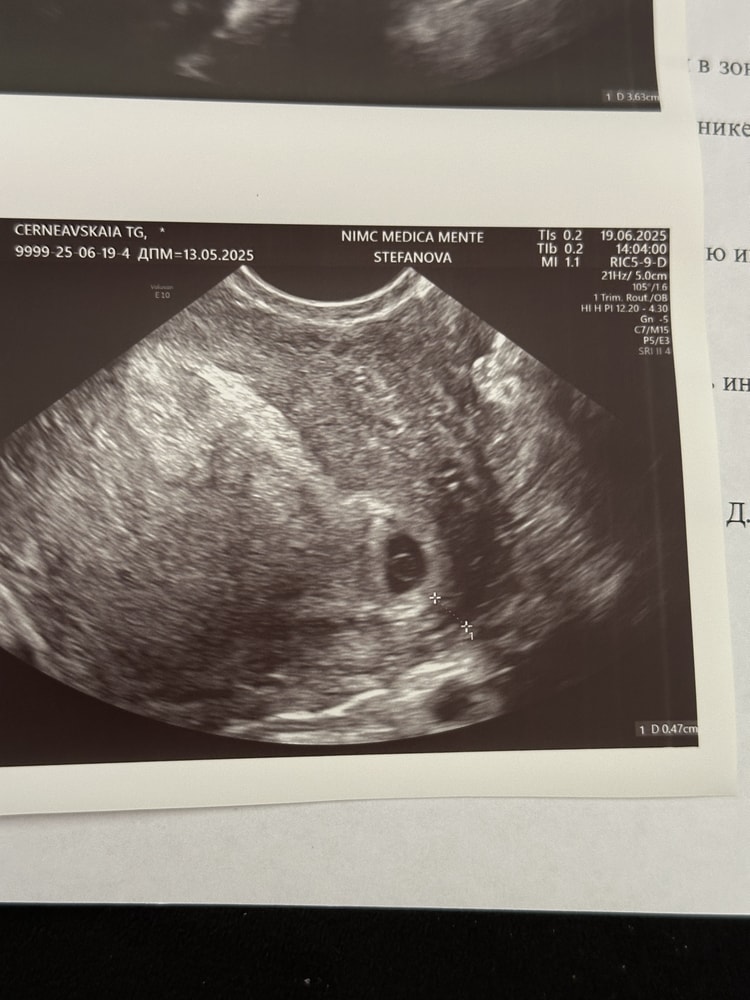

Пришла на узи чтобы убедиться что все в порядке

Но врач расстроил, ПЯ находится в матке, но совсем рядом с маточной трубой. Повторный визит 22.07. Если пя переместиться, то все хорошо, если нет, то операция

очень расстроилась, прикрепила протокол обследования. Может у кого то была подобная история с хорошим концом? Поделитесь пожалуйста